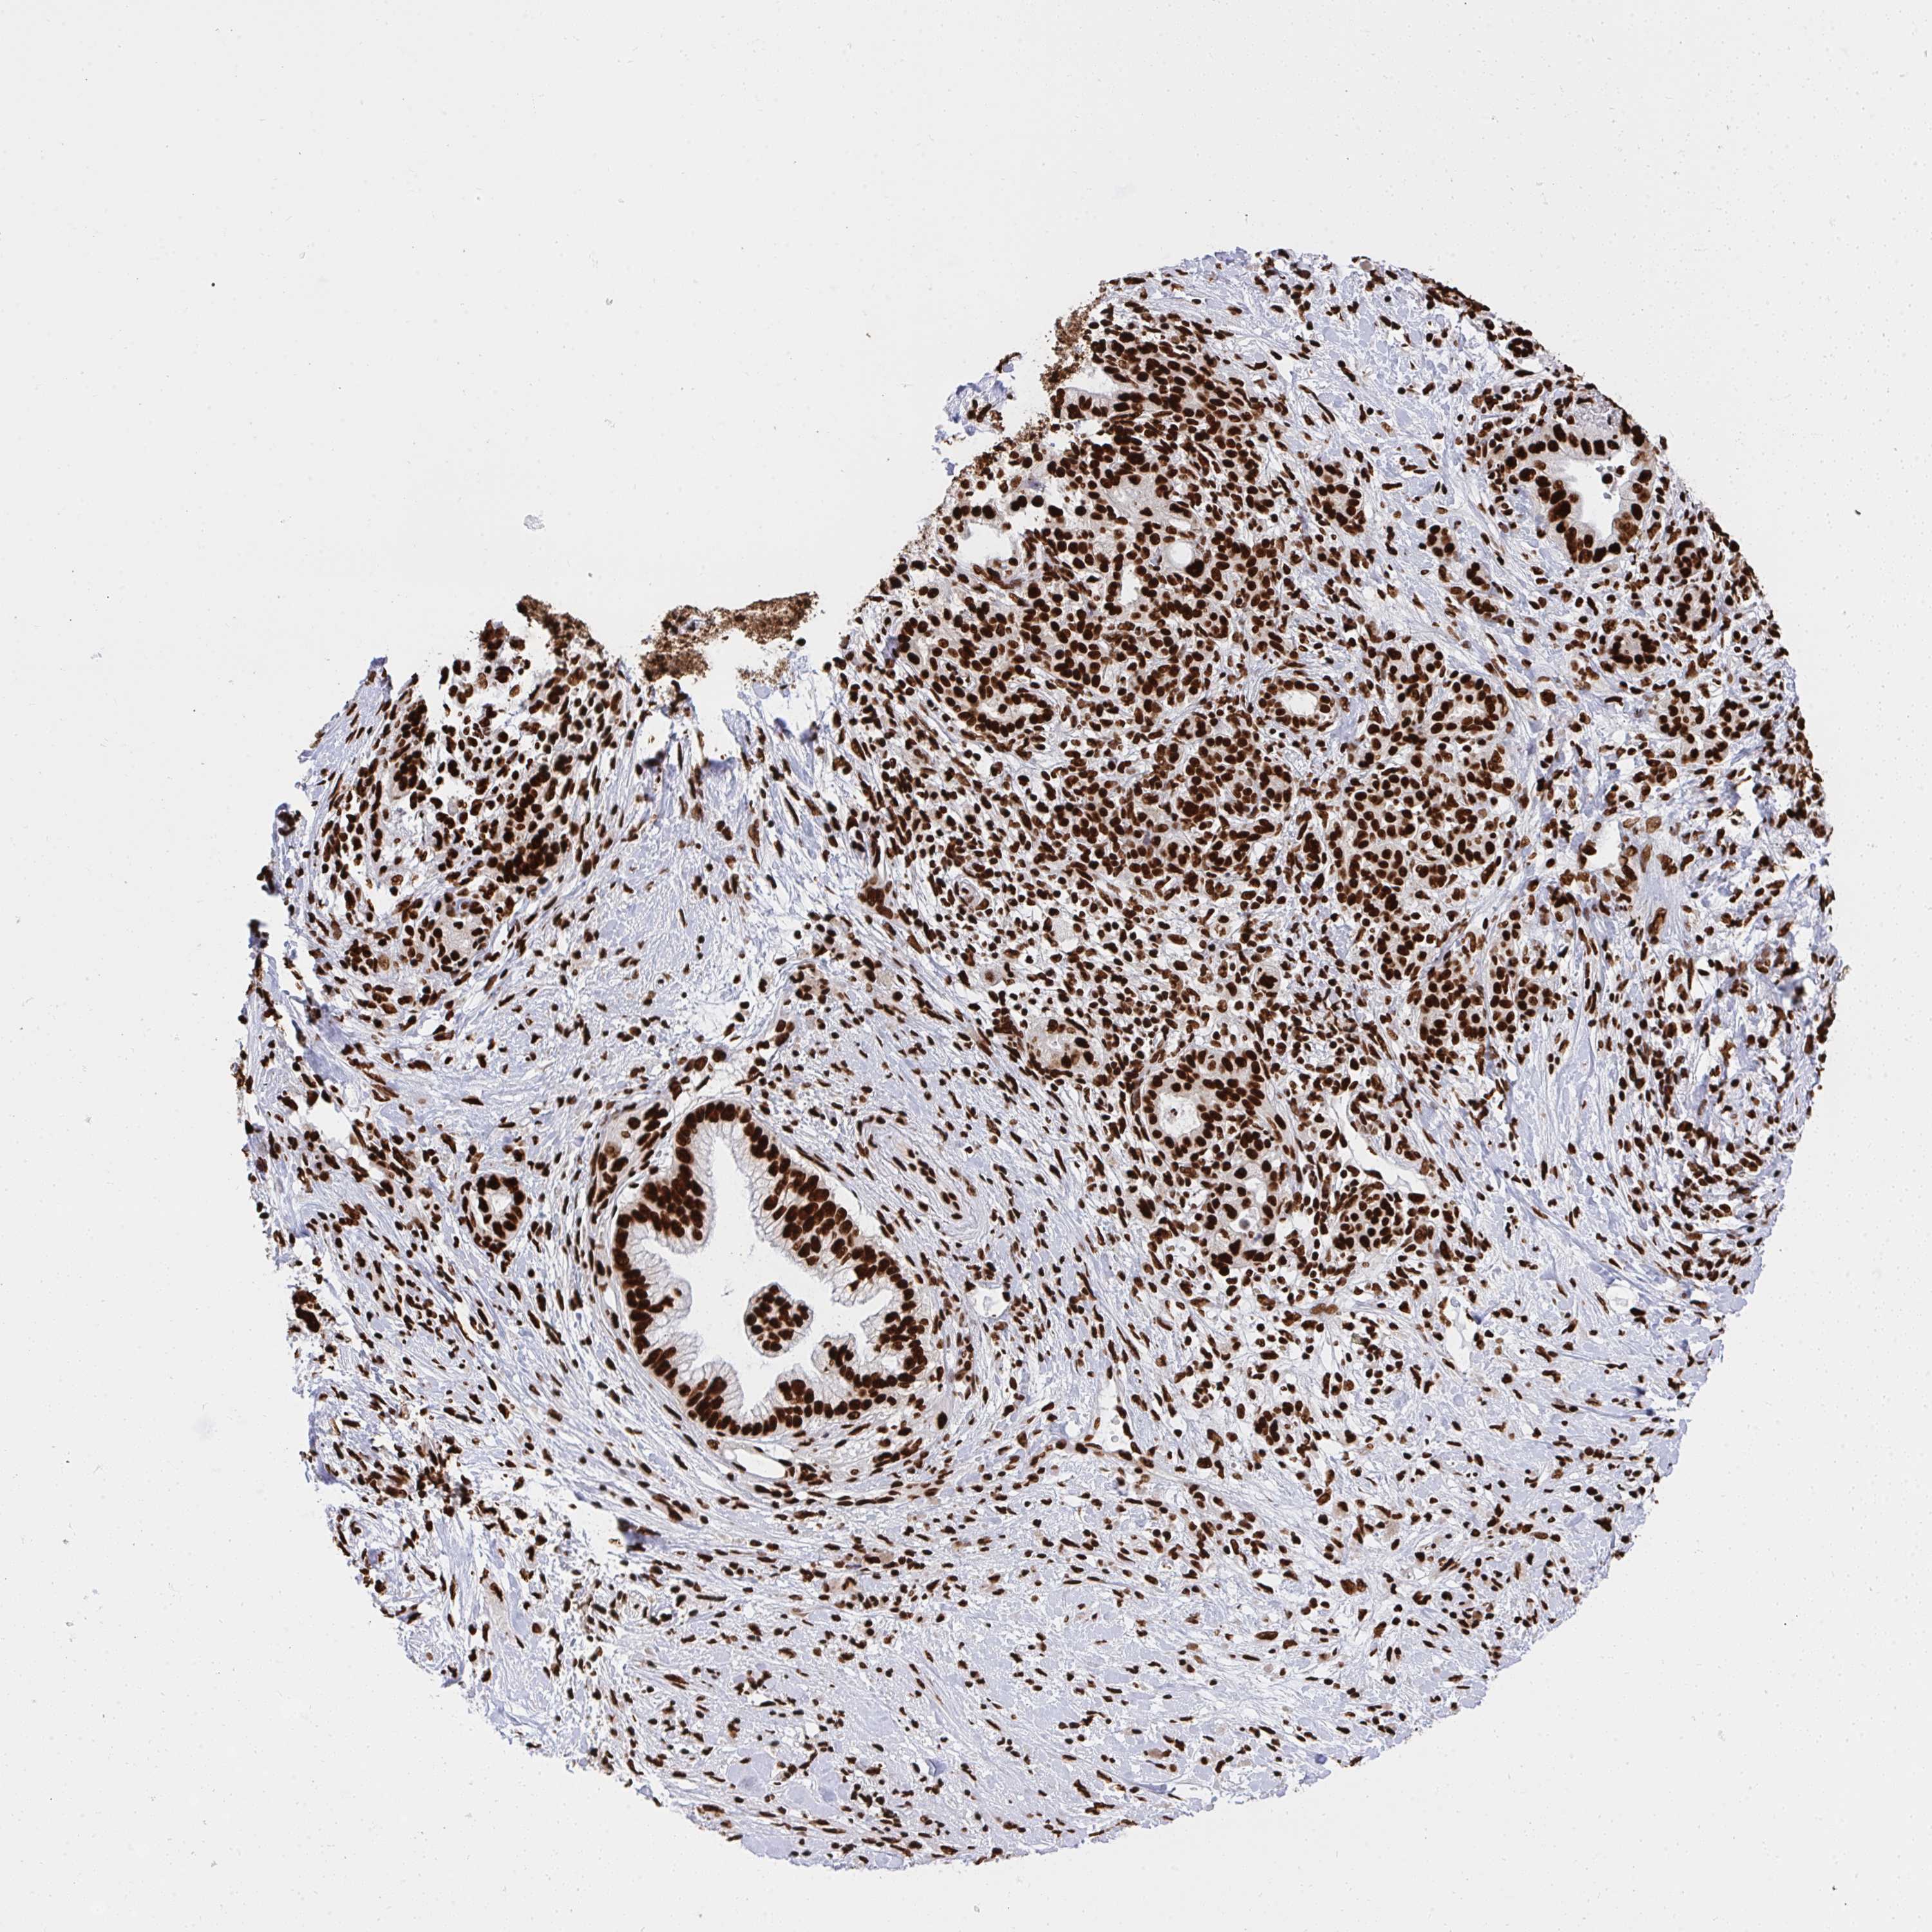

PANCREATIC CANCER - Protein expressioni

A mouse-over function shows sample information and annotation data. Click on an image to view it in a full screen mode. Samples can be filtered based on level of antibody staining by selecting one or several of the following categories: high, medium, low and not detected. The assay and annotation is described here.

Note that samples used for immunohistochemistry by the Human Protein Atlas do not correspond to samples in the TCGA dataset.

Antibody stainingi

Antibody staining in the annotated cell types in the current human tissue is reported as not detected, low, medium, or high, based on conventional immunohistochemistry profiling in selected tissues. This score is based on the combination of the staining intensity and fraction of stained cells.

Each image is clickable and will lead to virtual microscopy that enables deeper exploration of all samples and also displays staining intensity scores, fraction scores and subcellular localization as well as patient and tissue information for each sample.

Antibody HPA051748

Antibody HPA052661

Antibody CAB016326

Staining

High

Medium

Low

Not detected

Intensity

Strong

Moderate

Weak

Negative

Quantity

>75%

75%-25%

<25%

None

Location

Nuclear

Cytoplasmic/membranous

Cytoplasmic/membranous,nuclear

Adenocarcinoma, NOS